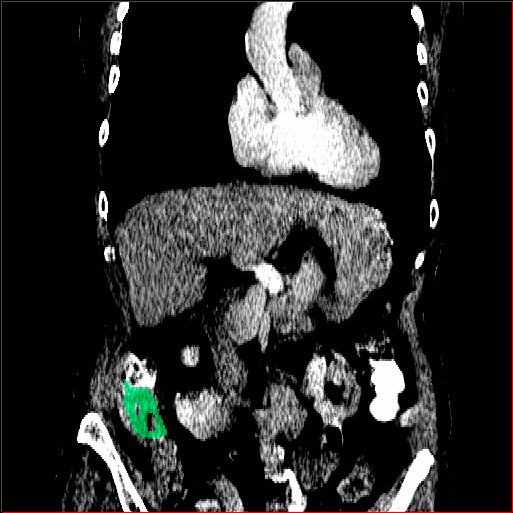

Figure 4 shows qualitatve results of MAISI-v2 ControlNet for different body regions and voxel sizes.

Chest Region

1×1×11\times 1\times 1

mm

384×384×384384\times 384\times 384

Abdomen Region

1×1×0.71\times 1\times 0.7

512×512×768512\times 512\times 768

Refer to caption

Figure 4: MAISI-v2 segmentation-guided results for small to large volume size and three different regions.